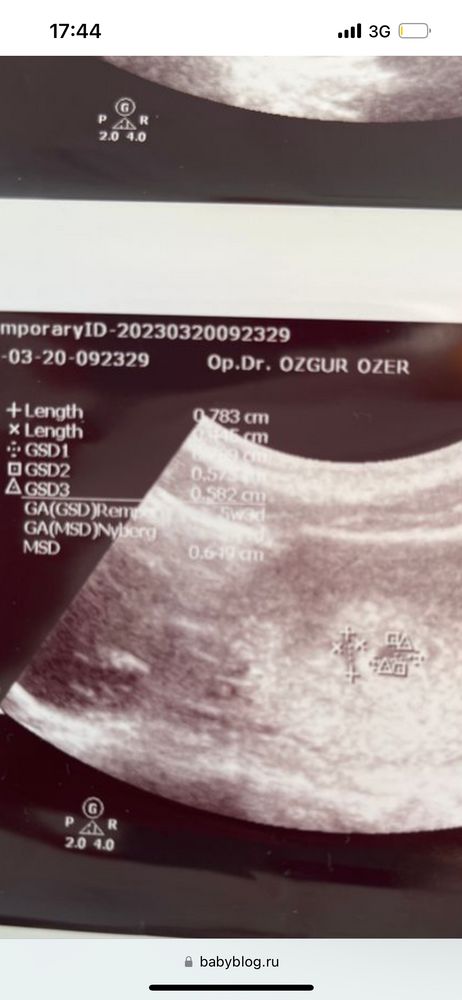

я даже не знаю, то что изображено (справа малыш, слева гематома) - там малыша увидели вообще? Или что это?

и нормально ли, что ЭТО на 5н3д - такого размера? 0,575Х0,582? И что гематома - по факту больше (0,7мм?)